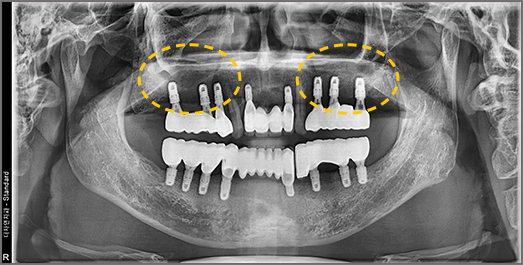

Full-Mouth Implant Restoration

Implant treatment for comprehensive full-arch restoration

This implant option is chosen to fully restore dental function. When missing teeth have been left untreated for an extended period,

the alveolar bone volume in both the maxilla and mandible is often insufficient. Therefore, a precise surgical plan must be established

with careful consideration of each patient's overall health condition.

• BEFORE: 2022.12.15

• AFTER: 2023.02.23